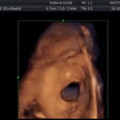

Բժիշկները ցույց են տվել՝ ինչպես է պտուղը «երգում» մոր արգանդում (լուսանկարներ) Շակիրան և ժերեր Պիկեն որդիների հետ Բարսելոնայում զբոսանքի են դուրս եկել (լուսանկարներ) Որտեղի՞ց է առաջացել «կեսարյան հատում» տերմինը Անհաջողակներ, ովքեր դաժանաբար սելֆիի զոհ դարձան (լուսանկարներ) Հայուհիներ, ովքեր փորձում են բարբի տիկնիկի նմանվել (լուսանկարներ) Հնէաբանական հայտնգործություններ, որոնք ժամանակակից գիտությունը ոչ մի կերպ չի կարողանում բացատրել (լուսանկարներ) Գիտնականները պարզել են, թե ինչպես է փոխվում կնոջ քաշն ամուսնության ընթացքում Կույսերը կարող են անձնական պատմության նոր էջ բացել. Հոկտեմբերի 9-ի աստղագուշակ Տասը խորհուրդ, որոնք կբարելավեն ձեր կյանքը 20 պատճառ, թե ինչու ես դեռ ամուսնացած չեմ Երեք հատկանիշ, որոնք տղամարդիկ ակնկալում են կանանցից Մոր ձեռքերում էր որդու գրեթե գլխատված մարմինը, սակայն 6 ժամ անց հրաշք տեղի ունեցավ Ինչու են ամուսնալուծվում Կենդանակերպի նշանները Պատմության ամենասարսափազդու դիկտատորների ու առաջնորդների՝ անհարմար պահին արված լուսանկարներ Ոչ մի դեպքում օծանելիքով մաշկը մի մերսեք, բույրը դրանից փոխվում է. Oծանելիքը ճիշտ օգտագործելու 7 կանոն Նազենին և Սոֆին բանի տեղ չեն դնում մարդկանց, իսկ Քրիստինե Պեպելյանը միայն VIP-ով է մեկնում. ինչպես են իրենց պահում հայտնիները օդանավակայանում Ինչպե՞ս է ազդում զայրույթը կյանքի տևողության վրա Հայտնի է ավելորդ քաշի և չափազանց շատ ուտելու պատճառները Ո՞վ է Մայա և Սոֆյա Պողոսյանների եղբայրը Թեստ, որը կպատմի Ձեր և Ձեր սիրո մասին Հովանոցը` ձեր ոճի և կերպարի կարևոր տարր Հետաքրքիր փաստեր շրթներկի մասին «Կլոն» հեռուստասերիալի Սամիրայի փարթամացած շքեղ մարմինը, ճոխ հարսանիքը և խայտառակ բաժանումը Ինչպես են տարիների ընթացքում փոխվել «Դոնիա Բարբարա» սերիալի դերասանները. լուսանկարներ Լուսանկարիչ, որը բացահայտում է լքված քաղաքները Աստղեր, ովքեր դպրոցում վերջին «լոխերն» են եղել, և նրանց հետ գրեթե ոչ ոք չի շփվել Կատարյալ մարմին՝ ընդամենը 10 րոպեում (լուսանկարներ) Facebook-ը պատրաստվում է ընդլայնել «լայք» կոճակի հնարավորությունները Լուսանկարներ, որ արվել են անխուսափելի իրադարձություններից 1 վայրկյան առաջ Մարտ Բաբայան. «Երբ ասում էի, որ ազգանունս Բաբայան է, ինձ տուգանում էին»